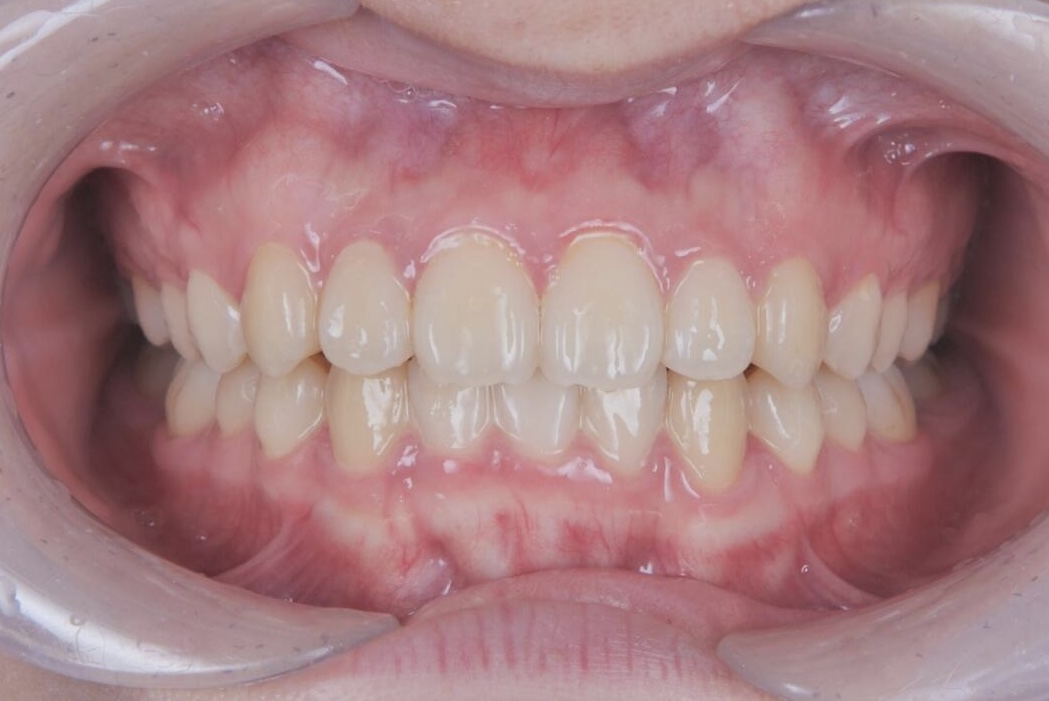

AFTER

治療は、マウスピース矯正インビザラインにて矯正治療を行い、歯列全体のバランスを考慮しながら計画を立てました。治療期間は1年4ヶ月で、歯並びがきれいに整っています。

見た目の自然さと治療中の快適さの両立を重視しながら、無理なく治療を進めることができた症例です。